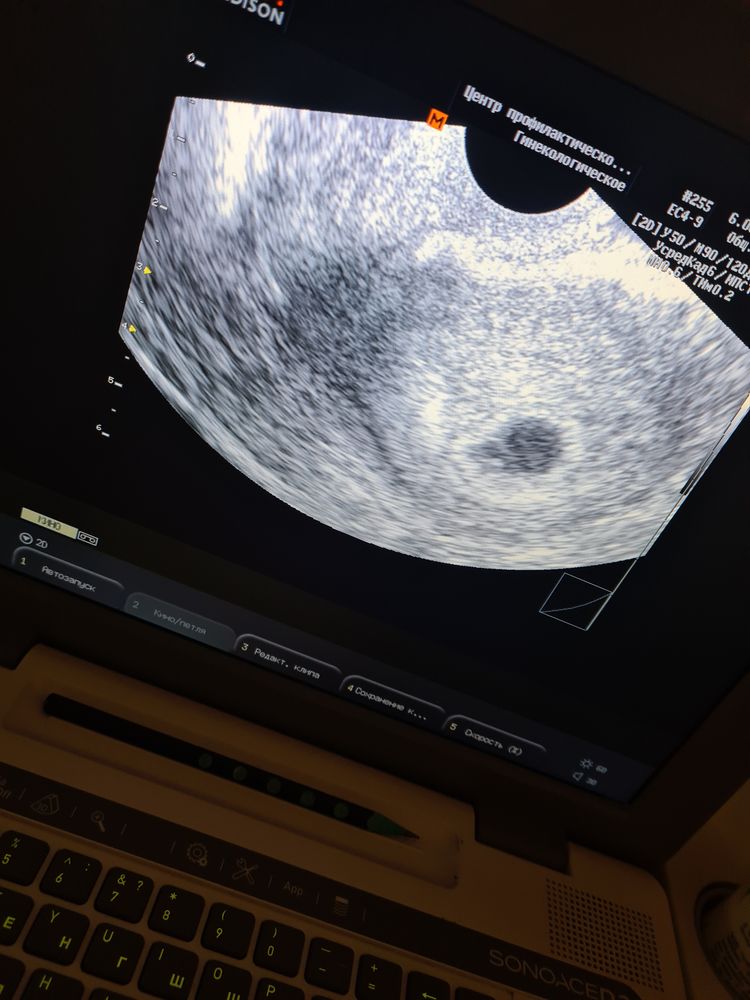

Первое узи❤️🥰растёт бусинка🙏

Дождалась наконец-то первого узи,ПЯ на месте,тьфу тьфу никаких проблем нету,26 числа иду вставать на учёт 🙏💫входим в режим ожидания)))самочувствие отличное не тошнит даже😁только все время хочу спать,расскажите как вы себя чувствовали?и как думаете кто будет?)))были ли беременные заскоки у вас?